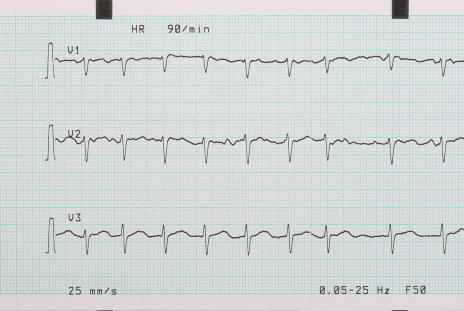

Arythmie, palpitations gênantes ou examen du pouls, qui varie en force et en irrégularité, voire un pouls inférieur à la fréquence cardiaque.

Anomalies 2. arythmies

Lorsque la fonction cardiaque décline et que certaines maladies cardiaques surviennent, les battements réguliers du cœur peuvent être interrompus, ce qui entraîne un rythme cardiaque irrégulier, particulièrement perceptible la nuit pendant le sommeil.

Lorsque vous constatez que votre arythmie est très évidente, il est préférable de vous rendre à l'hôpital pour un examen approfondi afin de déterminer s'il existe une maladie cardiaque et de la détecter et de la traiter à un stade précoce.

1. douleur thoracique nocturne.Chez les patients souffrant d'une maladie coronarienne, il existe non seulement la manifestation typique de l'angine d'effort, mais aussi, dans certains cas, une angine nocturne spontanée. Ce type de patients, la nuit en raison du spasme de l'artère coronaire, peut apparaître dans l'état de repos de la douleur thoracique, et la durée est plus souvent, commun dans le tabagisme et d'autres patients, l'électrocardiogramme de la douleur thoracique était l'élévation du segment ST performance. Dans ce cas, le diltiazem en gélules à libération prolongée peut être pris au coucher et donner de meilleurs résultats.

5. autres.Chez les patients souffrant d'une maladie cardiaque, des arythmies telles que des palpitations et des battements de cœur rapides peuvent également être présentes, qui sont généralement clarifiées par un électrocardiogramme ambulatoire.